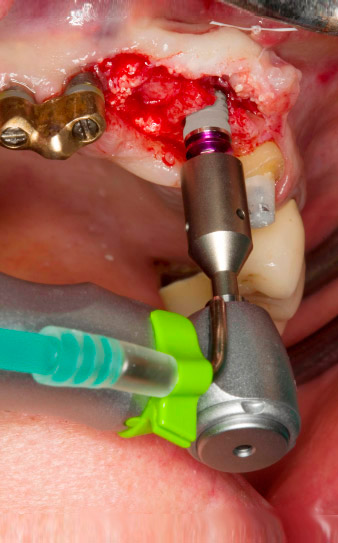

Une fois la cicatrisation primaire obtenue, les tissus mous ont été formés à l'aide du bridge doublé à la base. Deux mois plus tard, la zone a été exposée au moyen d'une incision de la crête alvéolaire légèrement orientée côté palatin (Fig 2). Les dimensions de l'os alvéolaire se sont avérées suffisantes en position 22. Les Figures 2 et 4 illustrent la préparation du lit implantaire, le taraudage et la pose de l'implant à l'aide de l'Implantmed.

Le nouveau moteur d'implantologie a été utilisé avec les contre-angles chirurgicaux de W&H correspondants.

WS-75 L suivant un ratio de 20:1 (programme P5).